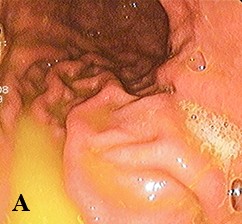

Рис. 2. А — трихобезоар желудкапредварительный диагноз «безоар желудка». В общем анализе крови отмечался гемоглобин 103 г/л. Другие лабораторные исследования в пределах нормы.

Проведена ЭГДС. Сразу при входе в желудок визуализировался волосяной шар (см. рис. 2а), при инсуффляции просвет желудка открывался мало. В теле желудка просвет заполнен волосяным образованием, которое продолжалось в антральный отдел. Слизистая оболочка не просматривалась, так как безоар почти полностью заполнял просвет. Далее он плотно входил в привратник, который с трудом удалось пройти эндоскопу. В просвете двенадцатиперстной кишки безоар тоньше, продолжался в тощую кишку.

Рис. 2.Б — удаленный трихобезоарЗаключение: трихобезоар желудка и тонкой кишки. Синдром Рапунцель.

Проведены лапаротомия, гастротомия. Удаленный безоар имел форму слепка желудка. По консистенции и внешнему виду напоминал плотный войлок, обладал гнилостным запахом, длина его хвоста составила около 50 см (см. рис. 2б).